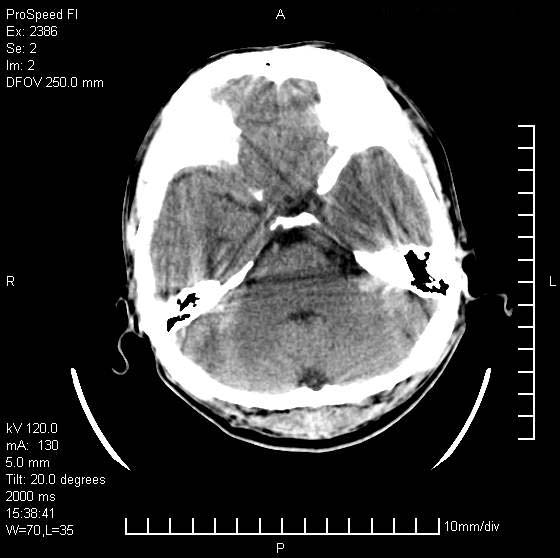

以下是引用天南地北在2007-9-19 18:43:00的发言:[br]典型慢性硬膜外血肿[br][br][本贴已被 天南地北 于 2007-9-19 18:44:11 修改过]

以下是引用曼一拍在2007-9-20 11:06:00的发言:[br]支持慢性硬膜下血肿.[br]慢性硬膜下积液:血肿有包膜,ct值稍高于脑脊液,增强可有染色。不典型者血肿可多呈梭形.是硬脑膜与蛛网膜之间的潜在腔隙内的血肿。[br]鉴别:[br]1\\硬膜外血肿:是颅脑外伤后脑膜或板障内血管破裂,血液在颅骨与硬膜之间积聚所致.通常是脑膜动脉破裂,也可因静脉窦破裂或颅骨的板障静脉出血,发生于外伤的着力部,常与颅骨骨折并存。脑膜动脉出血则急,若是板障静脉出血在则可有慢性。[br]2\\硬膜下积液:(硬膜下水瘤)[br]是由于蛛网膜破裂,脑脊液经蛛网膜破口进入硬膜下腔不能回流。或水肿阻塞而形成。[br]ct表现:颅骨内板下方新月形低密度区近似脑脊液密度;占位效应清,周围无脑水肿。[br]